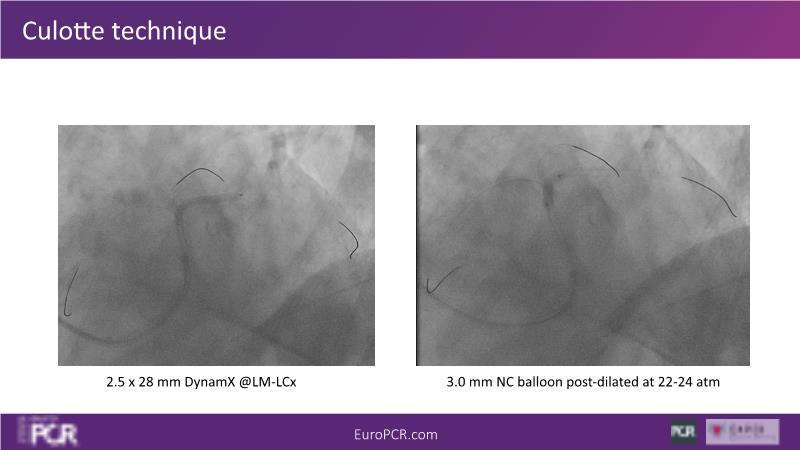

Join this session to delve into the unmet needs concerning drug-eluting stents (DES), including poor long-term clinical outcomes, with up to a 50% MACE rate at 10 years, and a non-plateauing 2-3% annual event rate. Explore how DynamX Bioadaptor technology addresses these challenges by maintaining the established flow lumen and restoring hemodynamic modulation of the artery. Discover the sustained clinical benefits demonstrated in a 2-year RCT, potentially establishing a new treatment standard for CAD patients. Gain insights into patient types benefiting most in clinical practice, such as those at higher risk of restenosis (e.g., LAD disease, long lesions, small vessels, co-morbidities), and younger patients with longer lifespans.